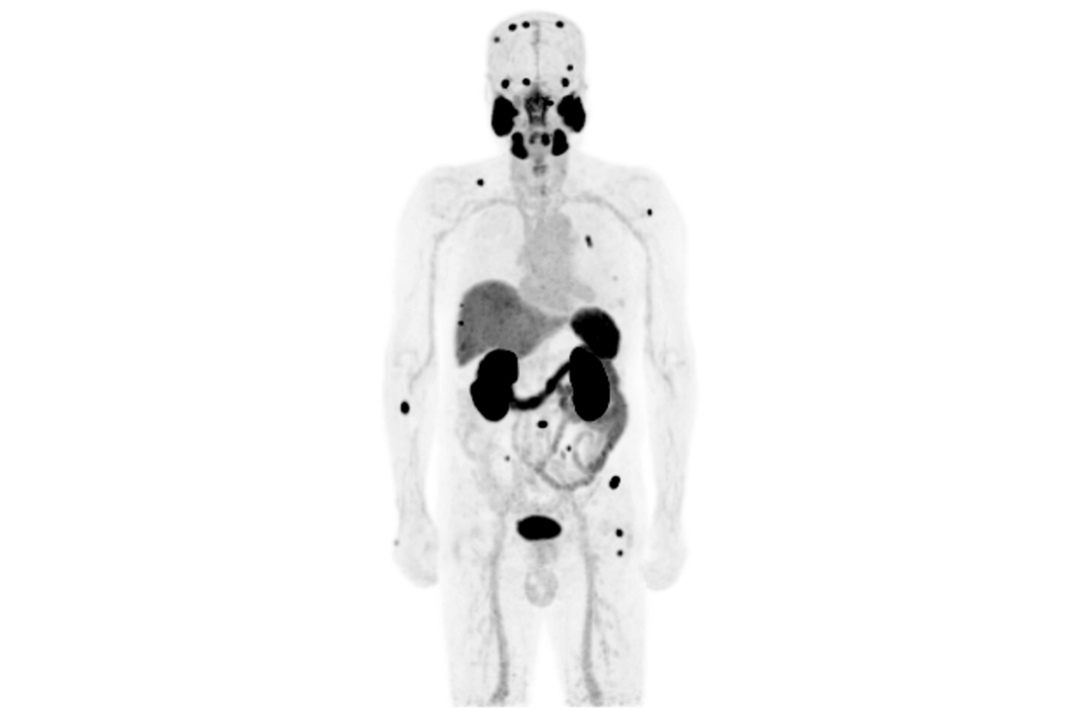

The TNM staging system is currently the most widely used staging system in the world. It can provide relevant information about the location, involvement and spread of the primary tumor through imagological examination methods. It's one of the most important examination methods to determine cancer staging. Integrated PET/MR perfectly combines molecular functions and structural images and serves as a vital means for the clinical diagnosis of tumors, cardiovascular disease, neurological disease, pediatric disease, and inflammatory disease.

However, since the launch of integrated PET/MR more than ten years ago, there have been limitations on  one of thscan efficiency. The short AFOV of PET fails to meet the needs of whole-body imaging, so it's been necessary to scan patients over multiple bed positions, which increases the scan time and reduces patient throughput.

Compared with the conventional PET system with AFOV ranging between 20cm and 25cm, the 32cm long AFOV not only improves the sensitivity of the system, but also basically covers main organs of the whole body and the regional lymphatic system where metastasis may occur, and makes it possible to realize cancer TN staging in one bed position.

In August 2019, Peking Cancer Hospital introduced United Imaging Healthcare's integrated PET/MR to make an in-depth exploration and optimization of cancer TNM staging under long AFOV. More than 500 examples of scanning various organs proved that long AFOV PET/MR could greatly increase the scan range over one bed position and improve the efficiency of cancer TNM staging.

The following are the cases of optimized TNM staging of breast cancer, esophageal cancer, prostate cancer and other diseases under the long axial field of "spatio-temporal integration" ULTRA-clear TOF PET/MR. Thanks to Capital Medical University Xuanwu Medical Treatment for providing the image.